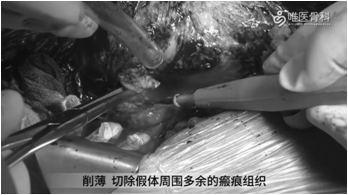

切除瘢痕组织:削薄并切除假体周围多余的瘢痕组织,常规行髋关节后脱位,并给予剥离股方肌与股外侧肌,去除围绕在假体与骨周围的瘢痕。